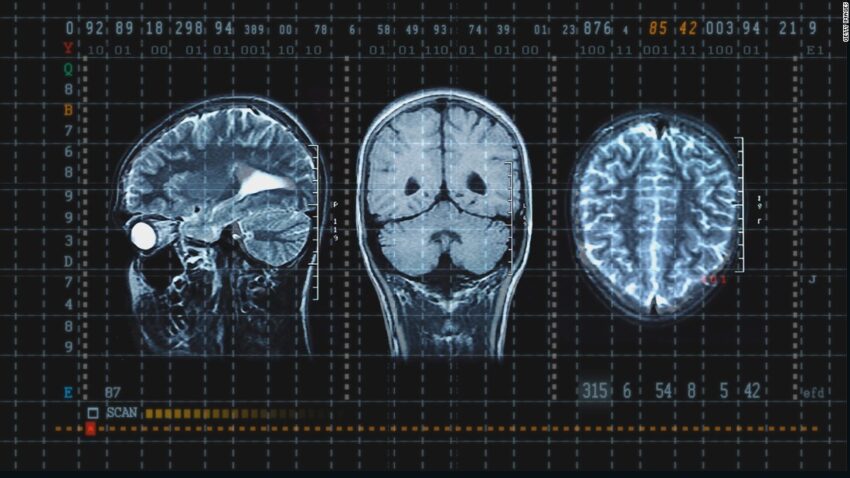

A concussion is a type of traumatic brain injury that occurs when the brain is shaken or jarred inside the skull. It is caused by a blow to the head or a sudden impact that causes the brain to move rapidly back and forth inside the skull. Concussions can cause a wide range of symptoms, including headache, dizziness, confusion, memory loss, and loss of consciousness.